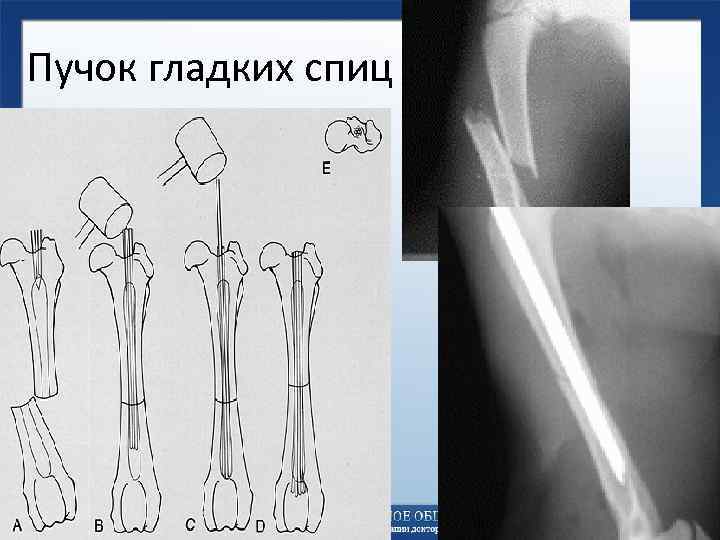

Пучок гладких спиц Пучок гладких спиц